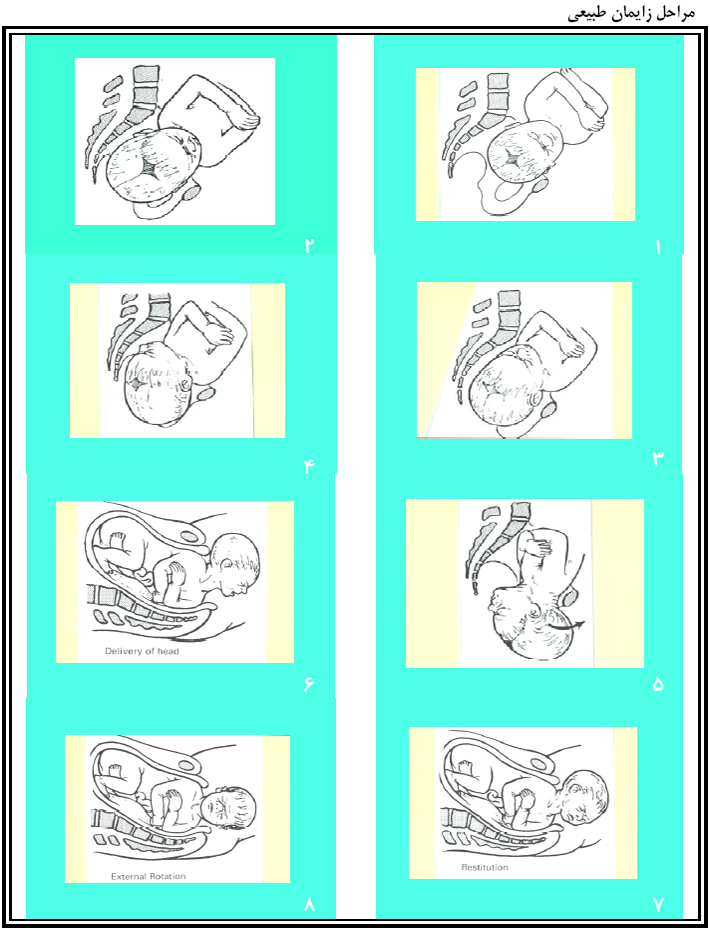

قیمت: 29٬000 تومان - دسته بندی فایل: علوم پزشکیزايمان، وضع حمل و نفاس

زايمان، وضع حمل و نفاس